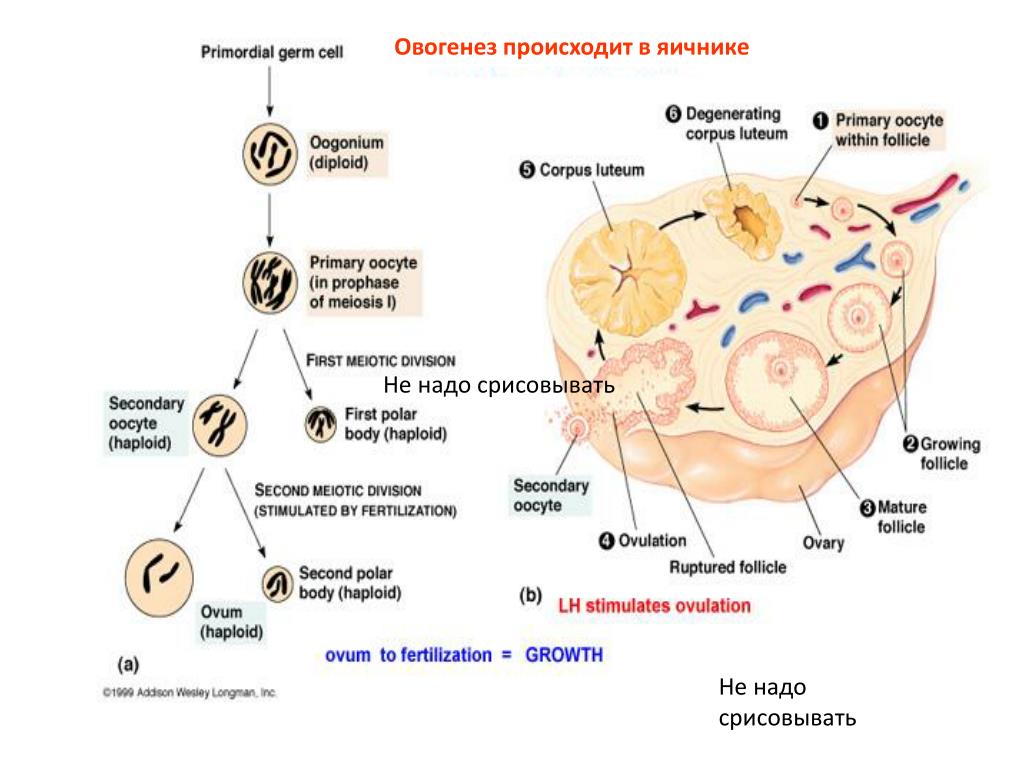

Созревание фолликула в яичнике: этапы и процессы